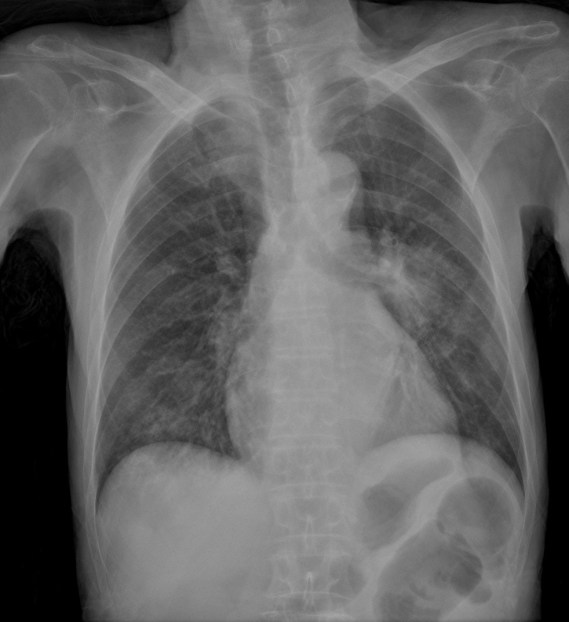

CASO: sospecha de neumonía.

Hallazgos:

- En un principio podríamos decir que existe un aumento de densidad retrocardiaco que podría ser compatible con condensación neumónica a dicho nivel, sin embargo estamos ante una placa poco inspirada, lo cual puede llevarnos a cometer errores diagnósticos.

- Se recomendó volver a realizar la radiografía, observar a continuación:

Ya no se observa el aumento de densidad retrocardiaco, la placa es normal.

INSPIRACIÓN: Una placa bien inspirada es aquella en la que se observar 6-7 arcos costales anteriores o 10-11 arcos costales posteriores. Lo contrario puede producir imágenes falsas de condensaciones o de seudocardiomegalia.